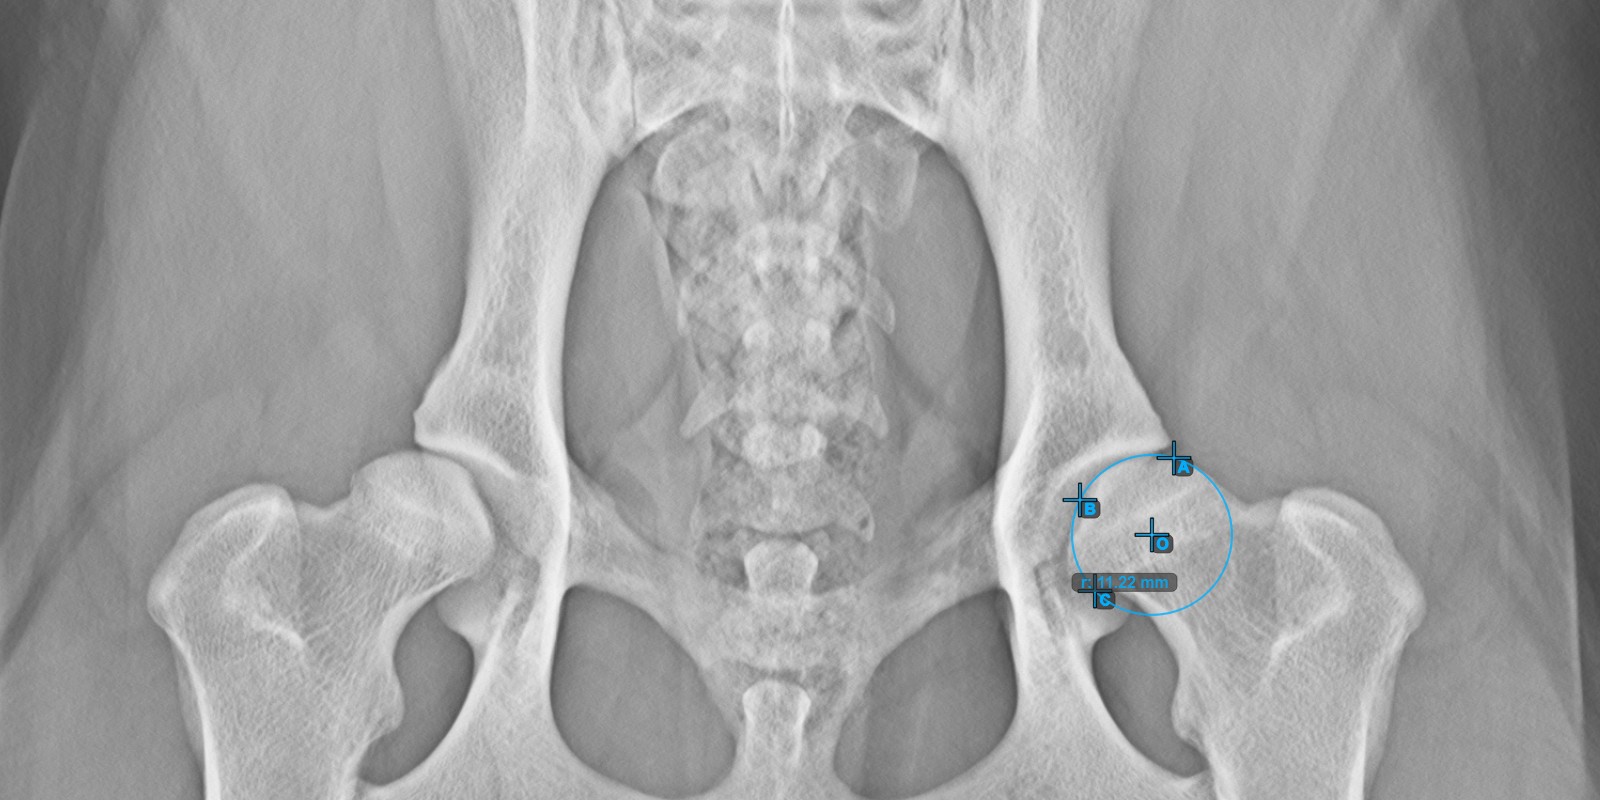

A lenti kép az **bal* Caput Femoris ízületi felszínén elhelyezett három pont tipikus elhelyezkedését ábrázolja.*

../../_images/image266.jpg